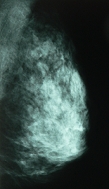

マンモグラフィとは何ですか?

乳房のX線撮影です。

乳房はとても柔らかい組織のため、専用のX線装置を使用します。

乳がんや乳房にできる病気をほとんど発見でき、しこりとして触れ

ないごく早期の乳がんも発見できます。